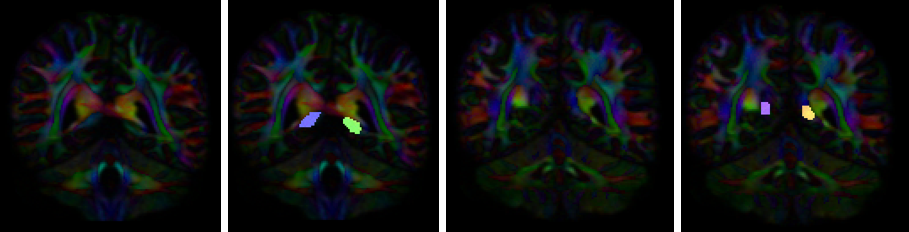

Instructions:

- Create two separate coronal seed regions (at approx. coronal slice 107): one for each side

- Create four separate coronal ROI regions (at approx. coronal slice 116 and 122): two for each side.

- Create one ROA region and draw a sagittal ROA slice at the midline (at approx. sagittal slice 78).

- Check the left seed/ROI regions and ROA region, then perform fiber tracking. Based on this output, the other ROA placements will be clearer.

- Using the same ROA file, draw 2-3 more regions:

- on a coronal slice anterior to seed/ROI regions (at approx. coronal slice 89)

- on optional coronal slices superior to the ROI regions.

- In the region list, check only the left seed region and ROA regions, then perform fiber tracking. Under the tract list, make sure only the desired left tract is checked and highlighted in purple. Save region, tract, and density files.

- Uncheck the left seed region and check the right seed region and ROA region, then perform fiber tracking. Under the tract list, make sure only the desired right tract is checked and highlighted in purple. Save region, tract, and density files.